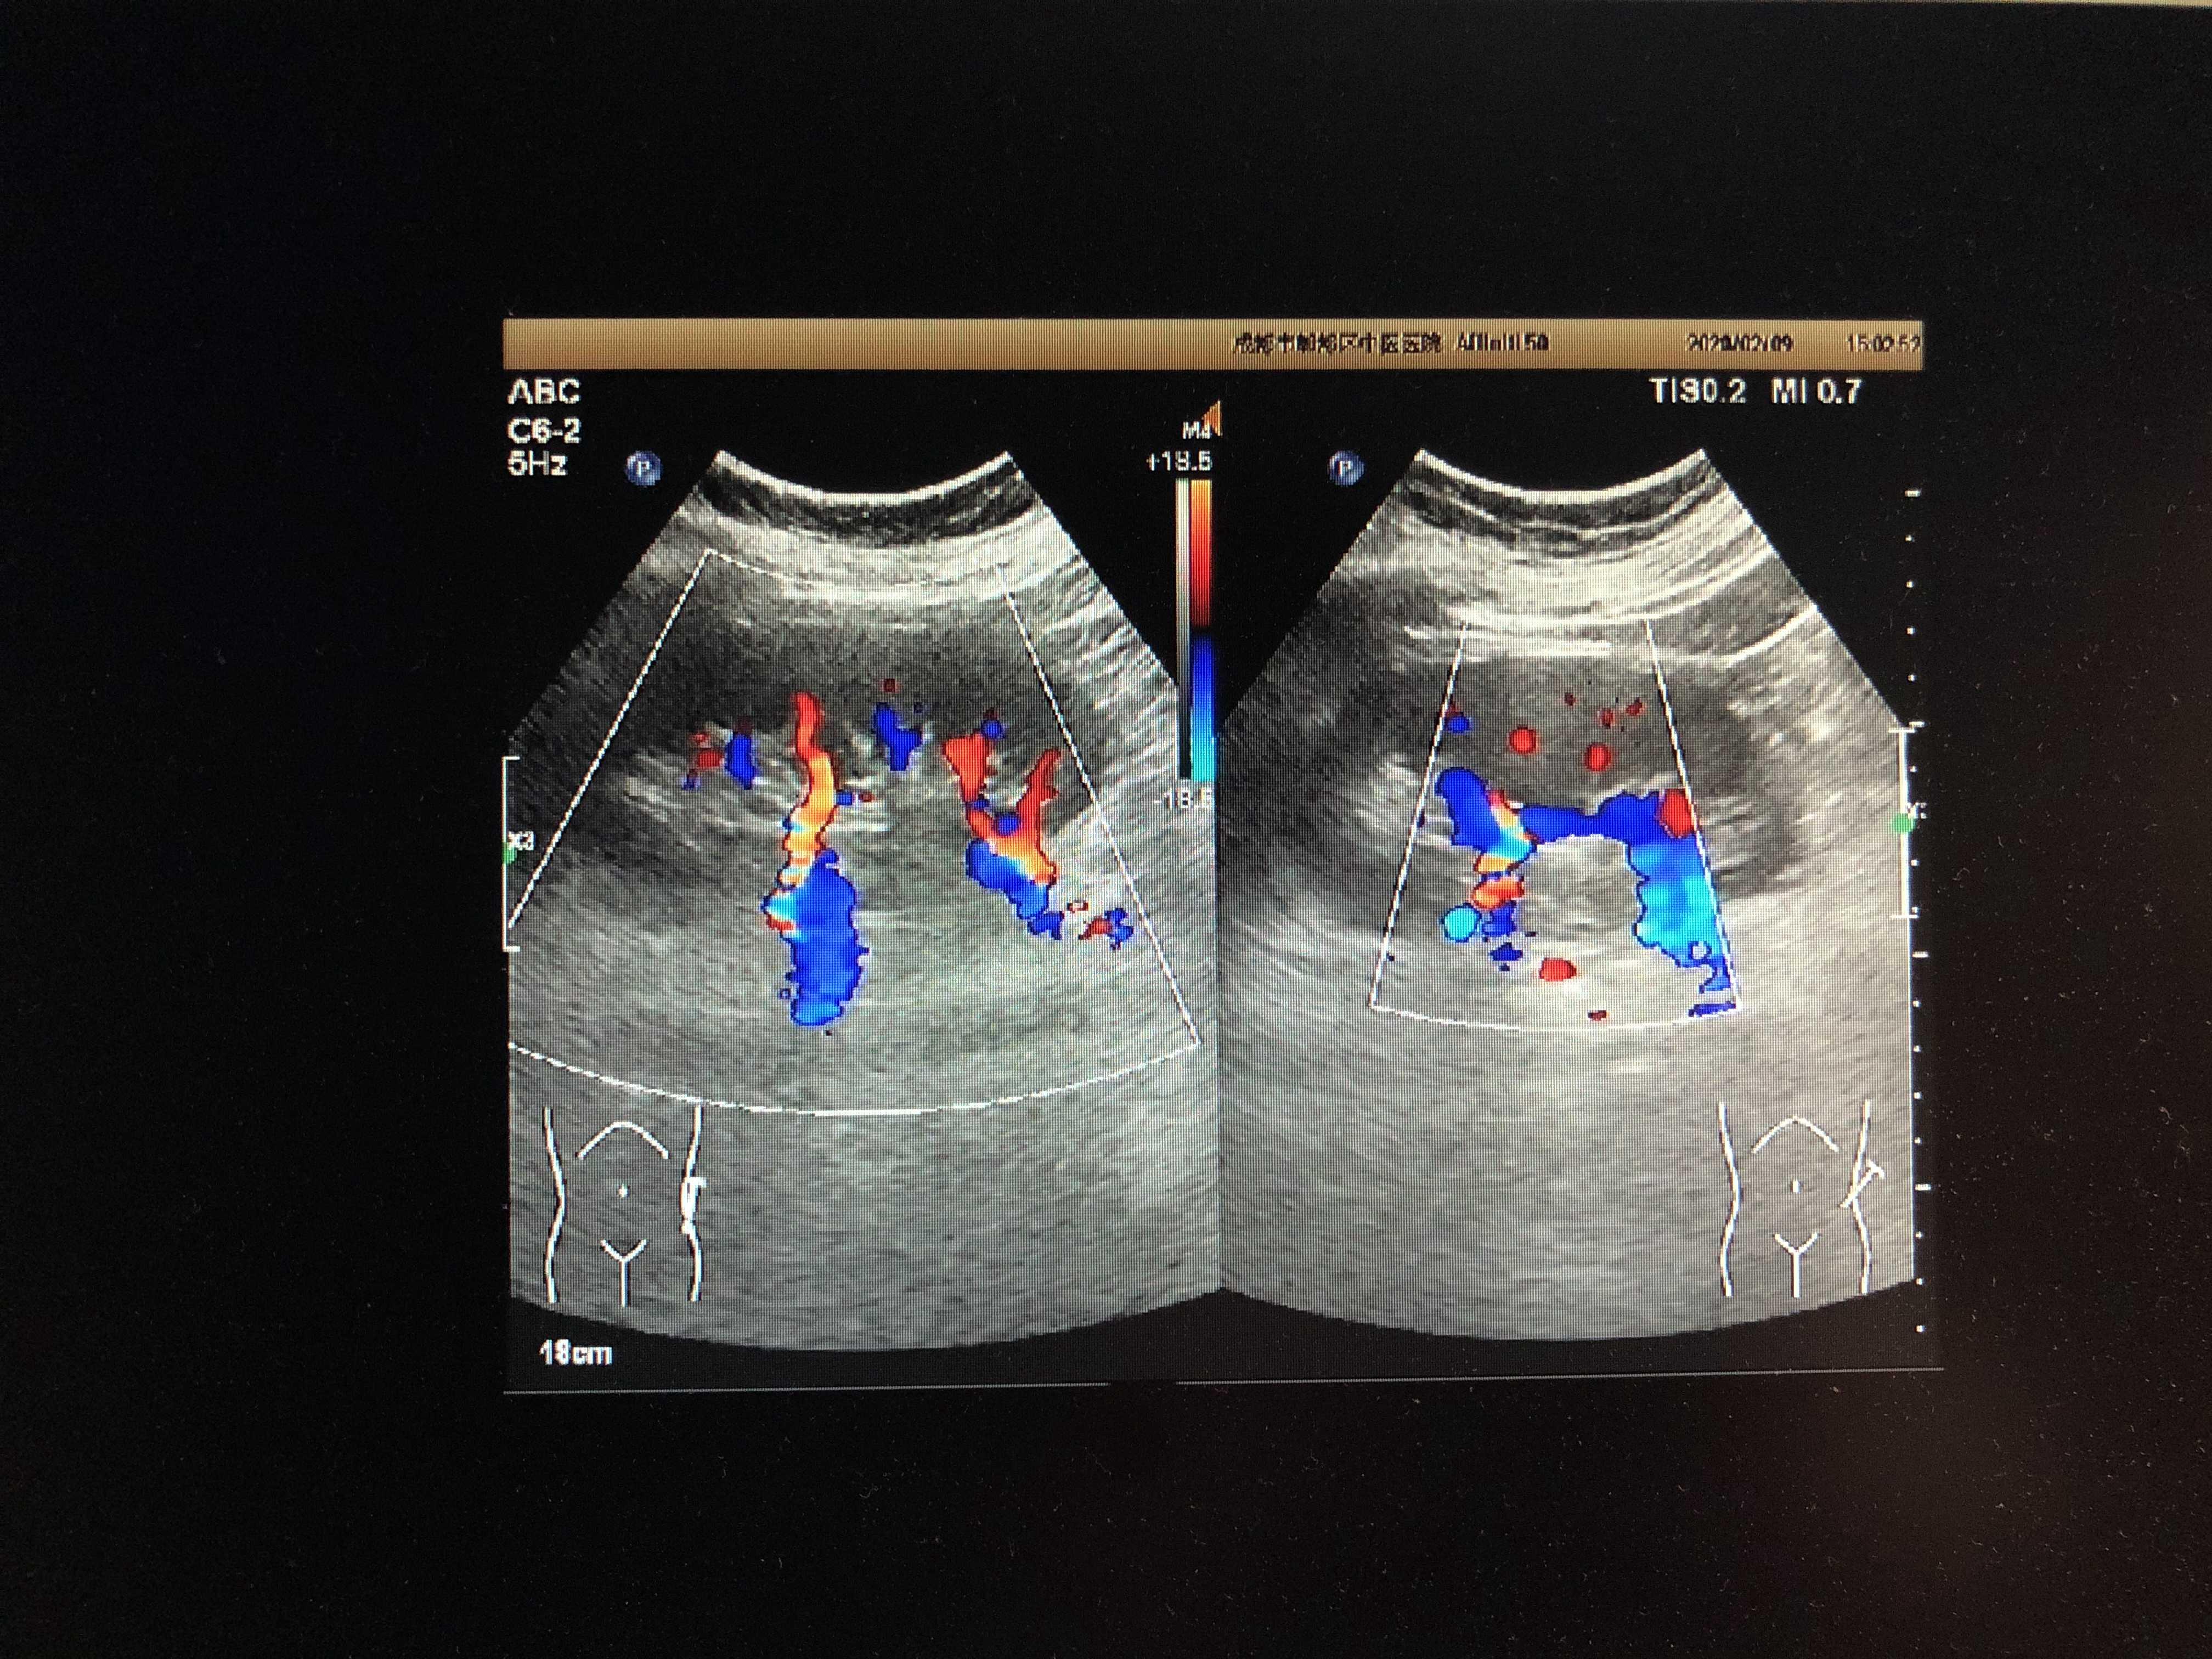

左肾副肾动脉 - 超声医学讨论版 - 爱爱医医学论坛

图片尺寸4032x3024